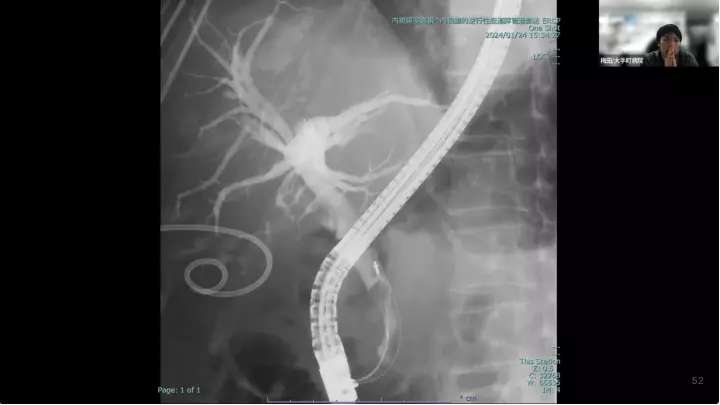

外科医目線の~急性胆嚢炎~治療編